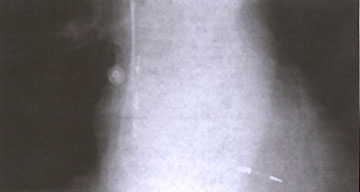

Figure 16e

Chest x-ray from a patient with a bipolar dual-chamber pacing system. The atrial lead is attached to the right atrial appendage by activefixation(screw-in lead), and the screw is visible on the chest x-ray. The ventricular lead is attached to the ventricle by passive fixation.